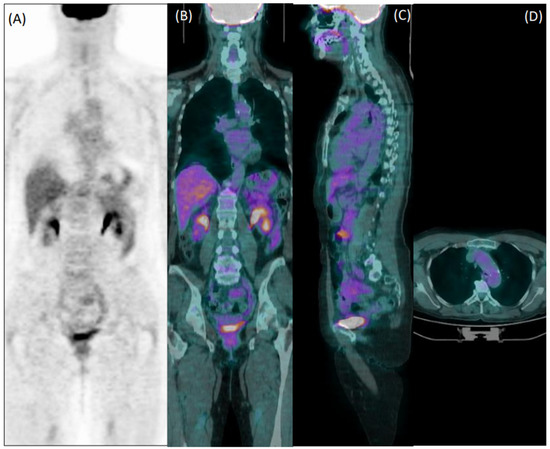

The diagnostic performance of reader 1 and reader 2 are detailed in Table 3 and Table 4, respectively. In the entire population, the sensitivity, specificity, accuracy, PPV, and NPP of reader 1 were 54%, 80%, 73%, 53, and 81%, respectively. The diagnostic performances of reader 2 were sensitivity = 59%, specificity = 70%, accuracy = 67%, PPV = 45%, and NPP = 81%. Figure 4a is a radar chart summarizing the performances for both readers considering the clinical diagnosis of vasculitis.

Overall, the interrater agreement for accuracy between the experienced nuclear medicine physician and the student was 71% with a Cohen’s Kappa value of 0.37 (fair agreement). A radar chart summarizing the performances of reader 2 against reader 1 is presented in Figure 4b.

Figure 4. (a) Interrater agreement with diagnosis. The blue and orange line represent the diagnostic performances of the experienced physician (reader 1) and the student (reader 2), respectively. (b) Interrater agreement of the student’s diagnostic performances against the experienced physician (green line).